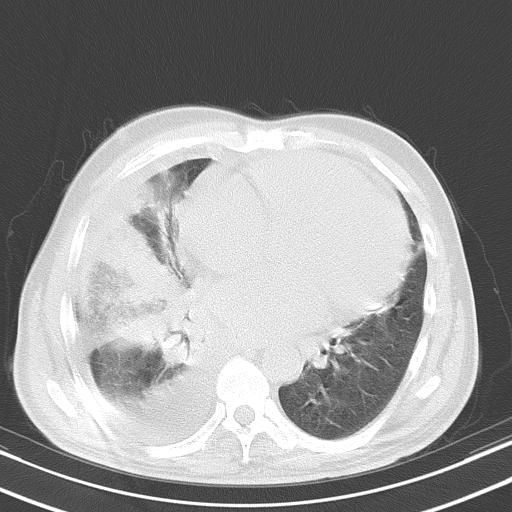

以下是引用zjzjr在2010-3-21 17:39:00的发言:[br]右下中心型肺癌并阻塞性肺炎/不张,纵膈淋巴结肿大,右侧大量胸腔积液,左侧少量胸腔积液

以下是引用zxl51642在2010-3-21 17:06:00的发言:[br]右下中心型肺癌并阻塞性肺炎/不张,纵膈淋巴结肿大,右侧大量胸腔积液,左侧少量胸腔积液,少量腹水。建议纤维支气管镜进一步检查。